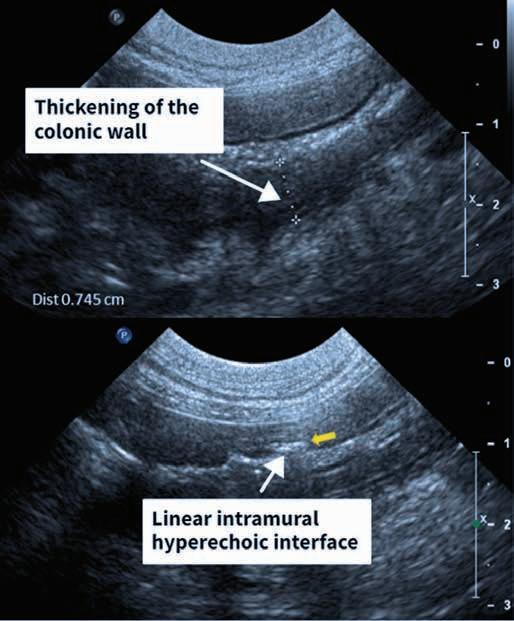

Probe orientation

thoracocentesis can be performed with the probe in a perpendicular orientation to the ribs, using an out-of-plane technique (see later), or a parallel orientation to the ribs using an in-plane technique. In-plane techniques with the probe parallel to the ribs are most commonly used for thoracocentesis in cats.

Procedure

l orientate the probe parallel to the ribs, over the widest accumulation of fluid with the indicator marker of the probe directed dorsally (Figure 7).

l Care should be taken to avoid inserting the needle at the caudal rib margins as the nerves and vessels are located here. t he needle should enter the centre to caudal third of the intercostal space.

ultrasound-guided thoracocentesis. The probe is usually held with the non-dominant hand. The dominant hand is used to manipulate and advance the needle/catheter. The ultrasound probe is placed between ribs where the deepest ultrasonographically visible pocket of pleural effusion is localised. The needle is inserted at an angle and advanced using ultrasound guidance until the tip is well situated within the pleural effusion. (Images courtesy of Drs J Menard and S Boysen)